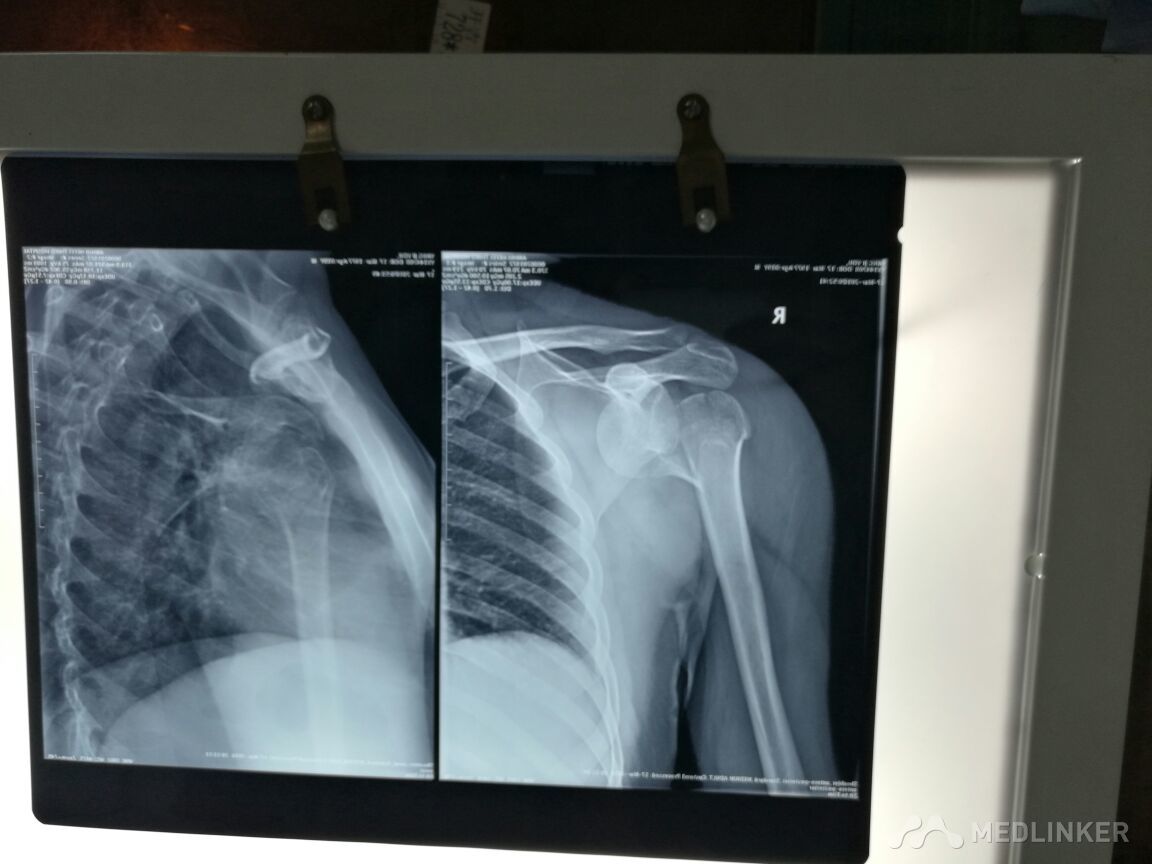

请教各位老师,这个病人手术方式,患者,男,39岁?

合肥瑞康骨科医院

发布于 16-03-17 21:56